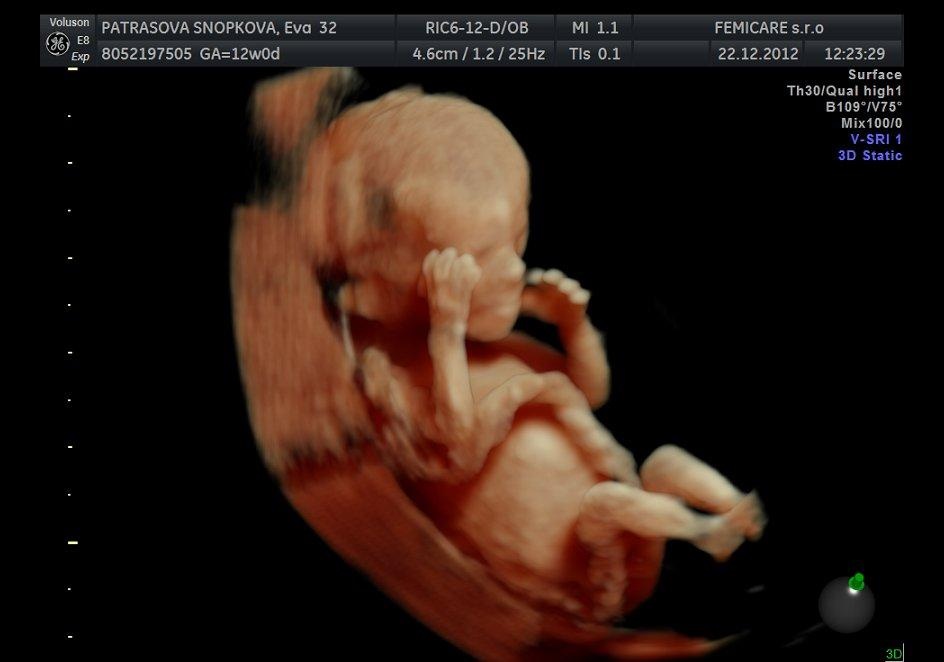

tak, po vcerajsej kontrole mame uz aj teh. knizku a zakladne vysetrenia. ten prcek prekypuje aktivitou ako divy, ani foto sa nedalo spravit co same kotrmelce robil... 😀

ahojte baby. Vcera som bola u doktora a upravil mi termin na 7. jula takze aj ja k vam patrim 🙂 v januari idem na testy ci nema babo nejaku poruchu a bude mi robit aj 3D 🙂 cakame prve babo tak dufam, ze bude vsetko v poriadku 🙂 ja idem dneska oznamovat tu radostnu novinu rodinke, tak dufam, ze to dobre dopadne 🙂

To je kraaaaaaaaaaaaaaaaaaaaaasa,uzasne babatko.Blahozelam. 🙂 Krasne je. 🙂

@michaelamia1902 ahoj,to ti robili uz 3D ultrazvuk?